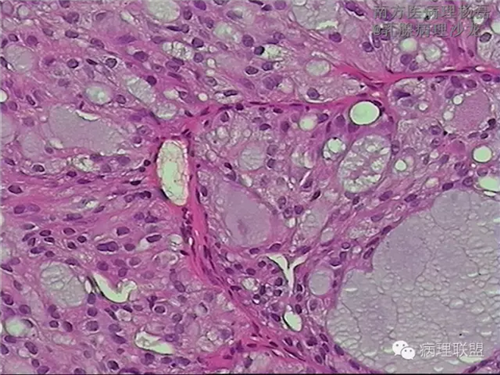

肺转移性乳腺分泌性癌?-病例讨论

女,51,右肺多发结节穿刺。15年前行右乳肿物切除,具体不详。